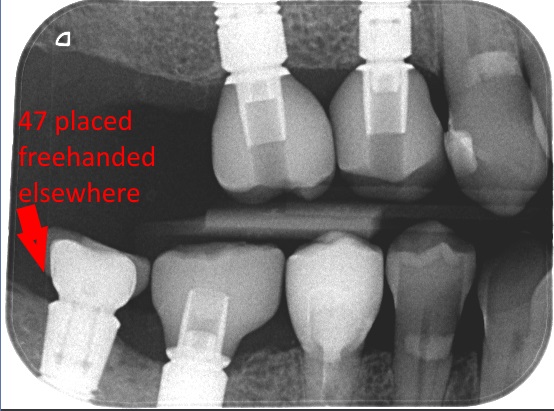

Alapuolelle oli asetettu vanhalla tekniikalla (kirurgin vapaalla kädellä) implantti rivin viimeiseksi. Kuten yleensä vapaalla kädellä tehtäessä implantin sijanti oli huono (tässä tapauksessa liian pinnassa) ja tämä näkyy metallin paljastumisena ja ärtyneenä ikenenä.  Vieressä on 3d ohjaimella laitettu implantti (toisiksi viimeinen hammas) josta huomaa näiden kahden tavan eroavaisuuden helposti! Kolmanneksi viimeinen hammas on Cercekillä tehty keraaminen kruunu.

IMG_7916f

alkkeffeef